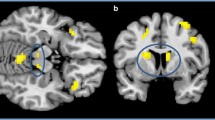

Patients with 22q11DS vs. healthy controls

During anticipation of reward, patients with 22q11DS, compared to controls, showed reduced activation (p FWE < 0.001) in a cluster (9271 voxels) covering the bilateral cingulate gyrus extending to premotor, primary motor and somatosensory areas (Table 3, Fig. 2a). During anticipation of loss, patients with 22q11DS showed reduced activation (p FWE < 0.05) in a cluster (3147 voxels) encompassing the left posterior cingulate cortex and extending bilaterally to the cuneus and precuneus (Table 3, Fig. 2b).

Within the 22q11DS group, anticipation of reward resulted in more activation of the right posterior cingulate and bilateral parietal regions in Val hemizygotes compared to Met hemizygotes (cluster size 3008 voxels, p FWE < 0.05, Table 4, Fig. 3a). Anticipation of loss resulted in significantly more activation in the bilateral insula, striatum and left anterior cingulate in Met hemizygotes compared to Val hemizygotes (Cluster size: 4481 voxels, Table 4, Fig. 3b).

To our knowledge, this is the first study to investigate the neural substrates of reward processing in people with 22q11DS, a population at high risk of developing a psychotic illness. Our main fMRI findings suggest that reward anticipation in 22q11DS engages a fronto-temporal network. Compared to healthy controls, people with 22q11DS primarily displayed reduced activity in medial frontal regions during reward anticipation. During anticipation of loss, a reduction in bilateral (pre)cuneus and left posterior cingulate activity was observed. Further analyses also revealed an effect of COMT genotype on the 22q11DS reward anticipation network.

The 22q11DS reward anticipation network seems different from healthy controls in several ways. During anticipation of reward, reduced activity in the cingulate gyrus and medial frontal brain regions was observed. These are all key structures of the reward circuitry in healthy controls [4, 6, 39, 41–43].

Decreased cingulate gyrus activity during reward anticipation could be related to impairments in predicting reward outcome, since this region is related to prediction error in reinforcement learning [44–46]. Reduced activation in medial frontal brain regions in 22q11DS during reward and posterior cingulate and (pre)cuneus brain regions during loss may be a reflection or consequence of the anatomical abnormalities typically seen in people with 22q11DS. These alterations include grey matter reductions in frontal and temporal regions and widespread white matter reductions primarily in the posterior lobe [47–51].